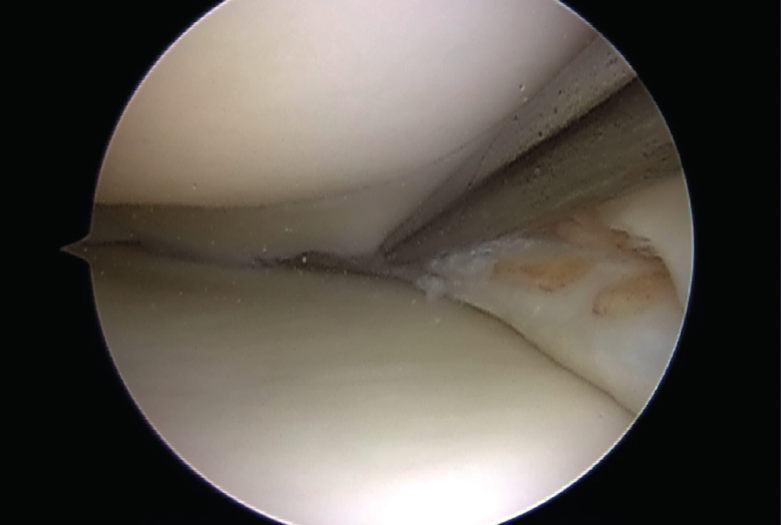

El tratamiento artroscópico de las lesiones meniscales está indicado en aquellas lesiones que produzcan bloqueo articular, pacientes sintomáticos que no mejoren con tratamiento conservador o aquellos en quienes se vea afectado su nivel deportivo o laboral (Figuras 1 y 2).

La artroscopia es considerada el patrón de oro para el diagnóstico, pero no está exenta de dificultades. El 40% de las lesiones en rampa no son identificadas a través de los portales anteriores estándares de visión, por lo que es necesario realizar una inspección del compartimento posterior a través de una visión transintercondílea o mediante un portal posteromedial(25,29).